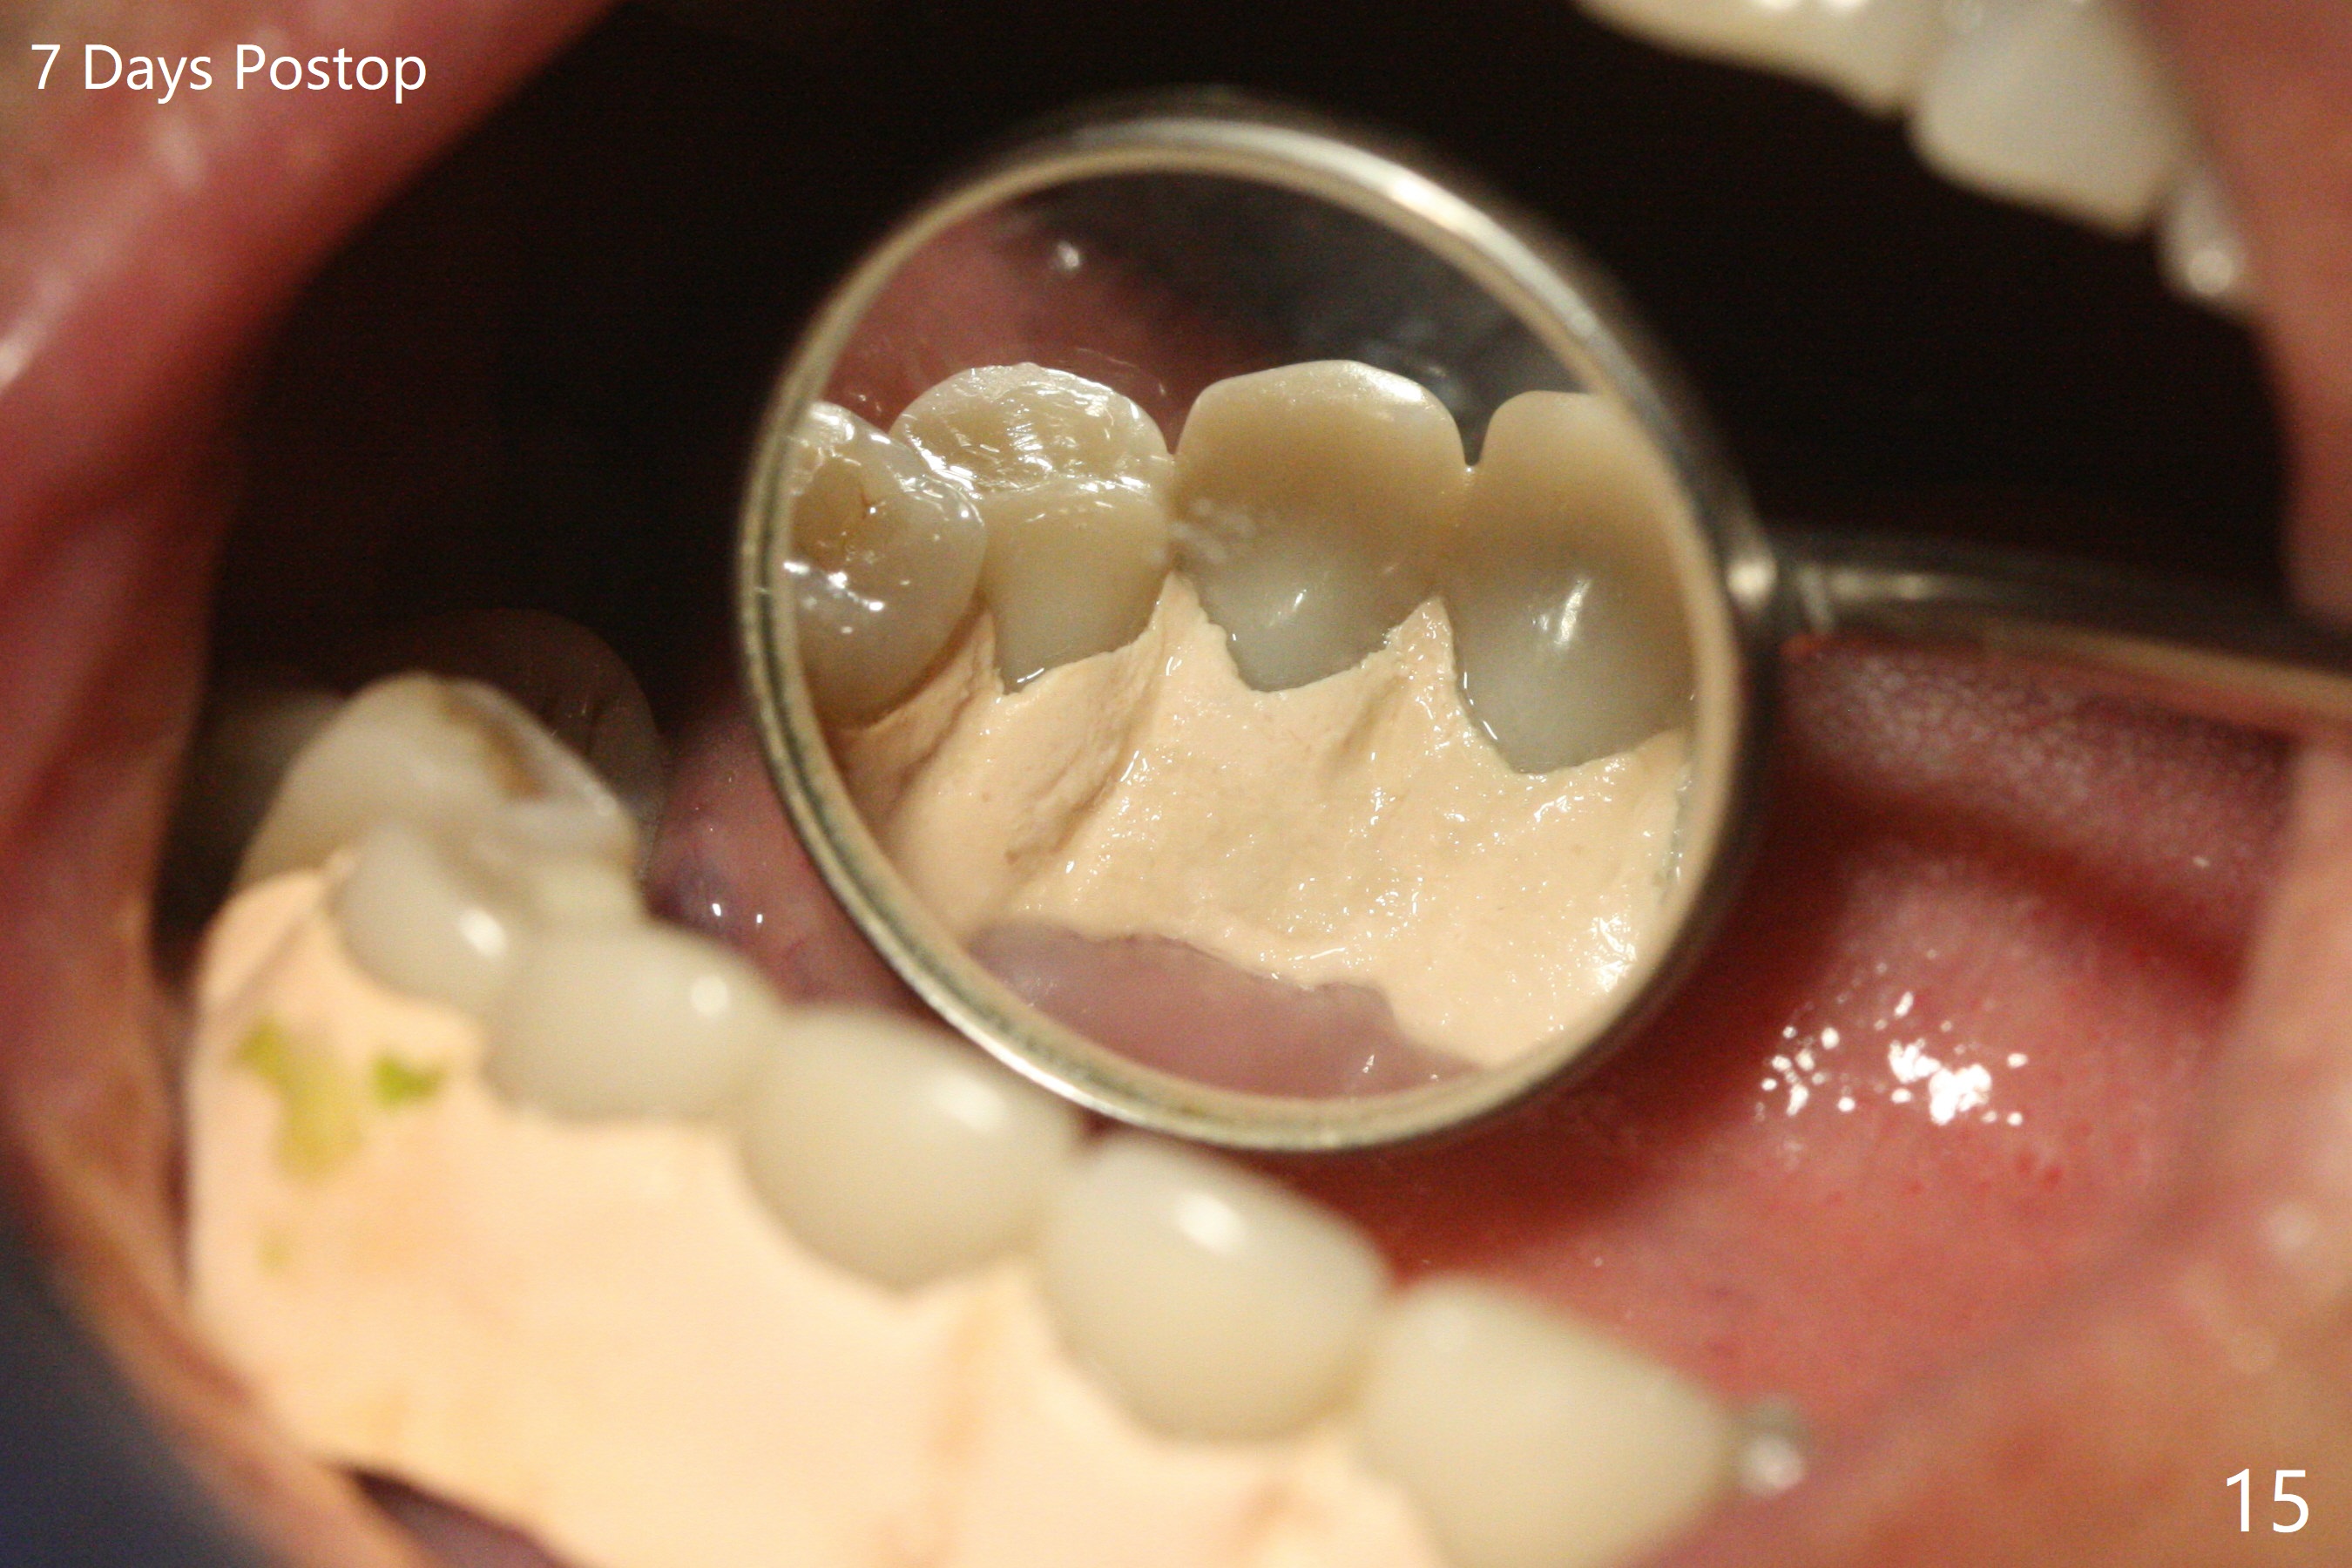

The implants remain asymptomatic years months post cementation (Fig.12), while the one at #27 is associated with buccal and lingual swelling and hemorrhage and bone loss (Fig.13). There is bone loss distal to #27 without symptom 3 years 9 months post cementation (Fig.12). Periimplantitis develops buccal and lingual 4 years 5 months post cementation (coronavirus, Fig.13). Sticky bone and PRF are used after debridement. There is no discomfort 7 days postop (Fig.14,15).